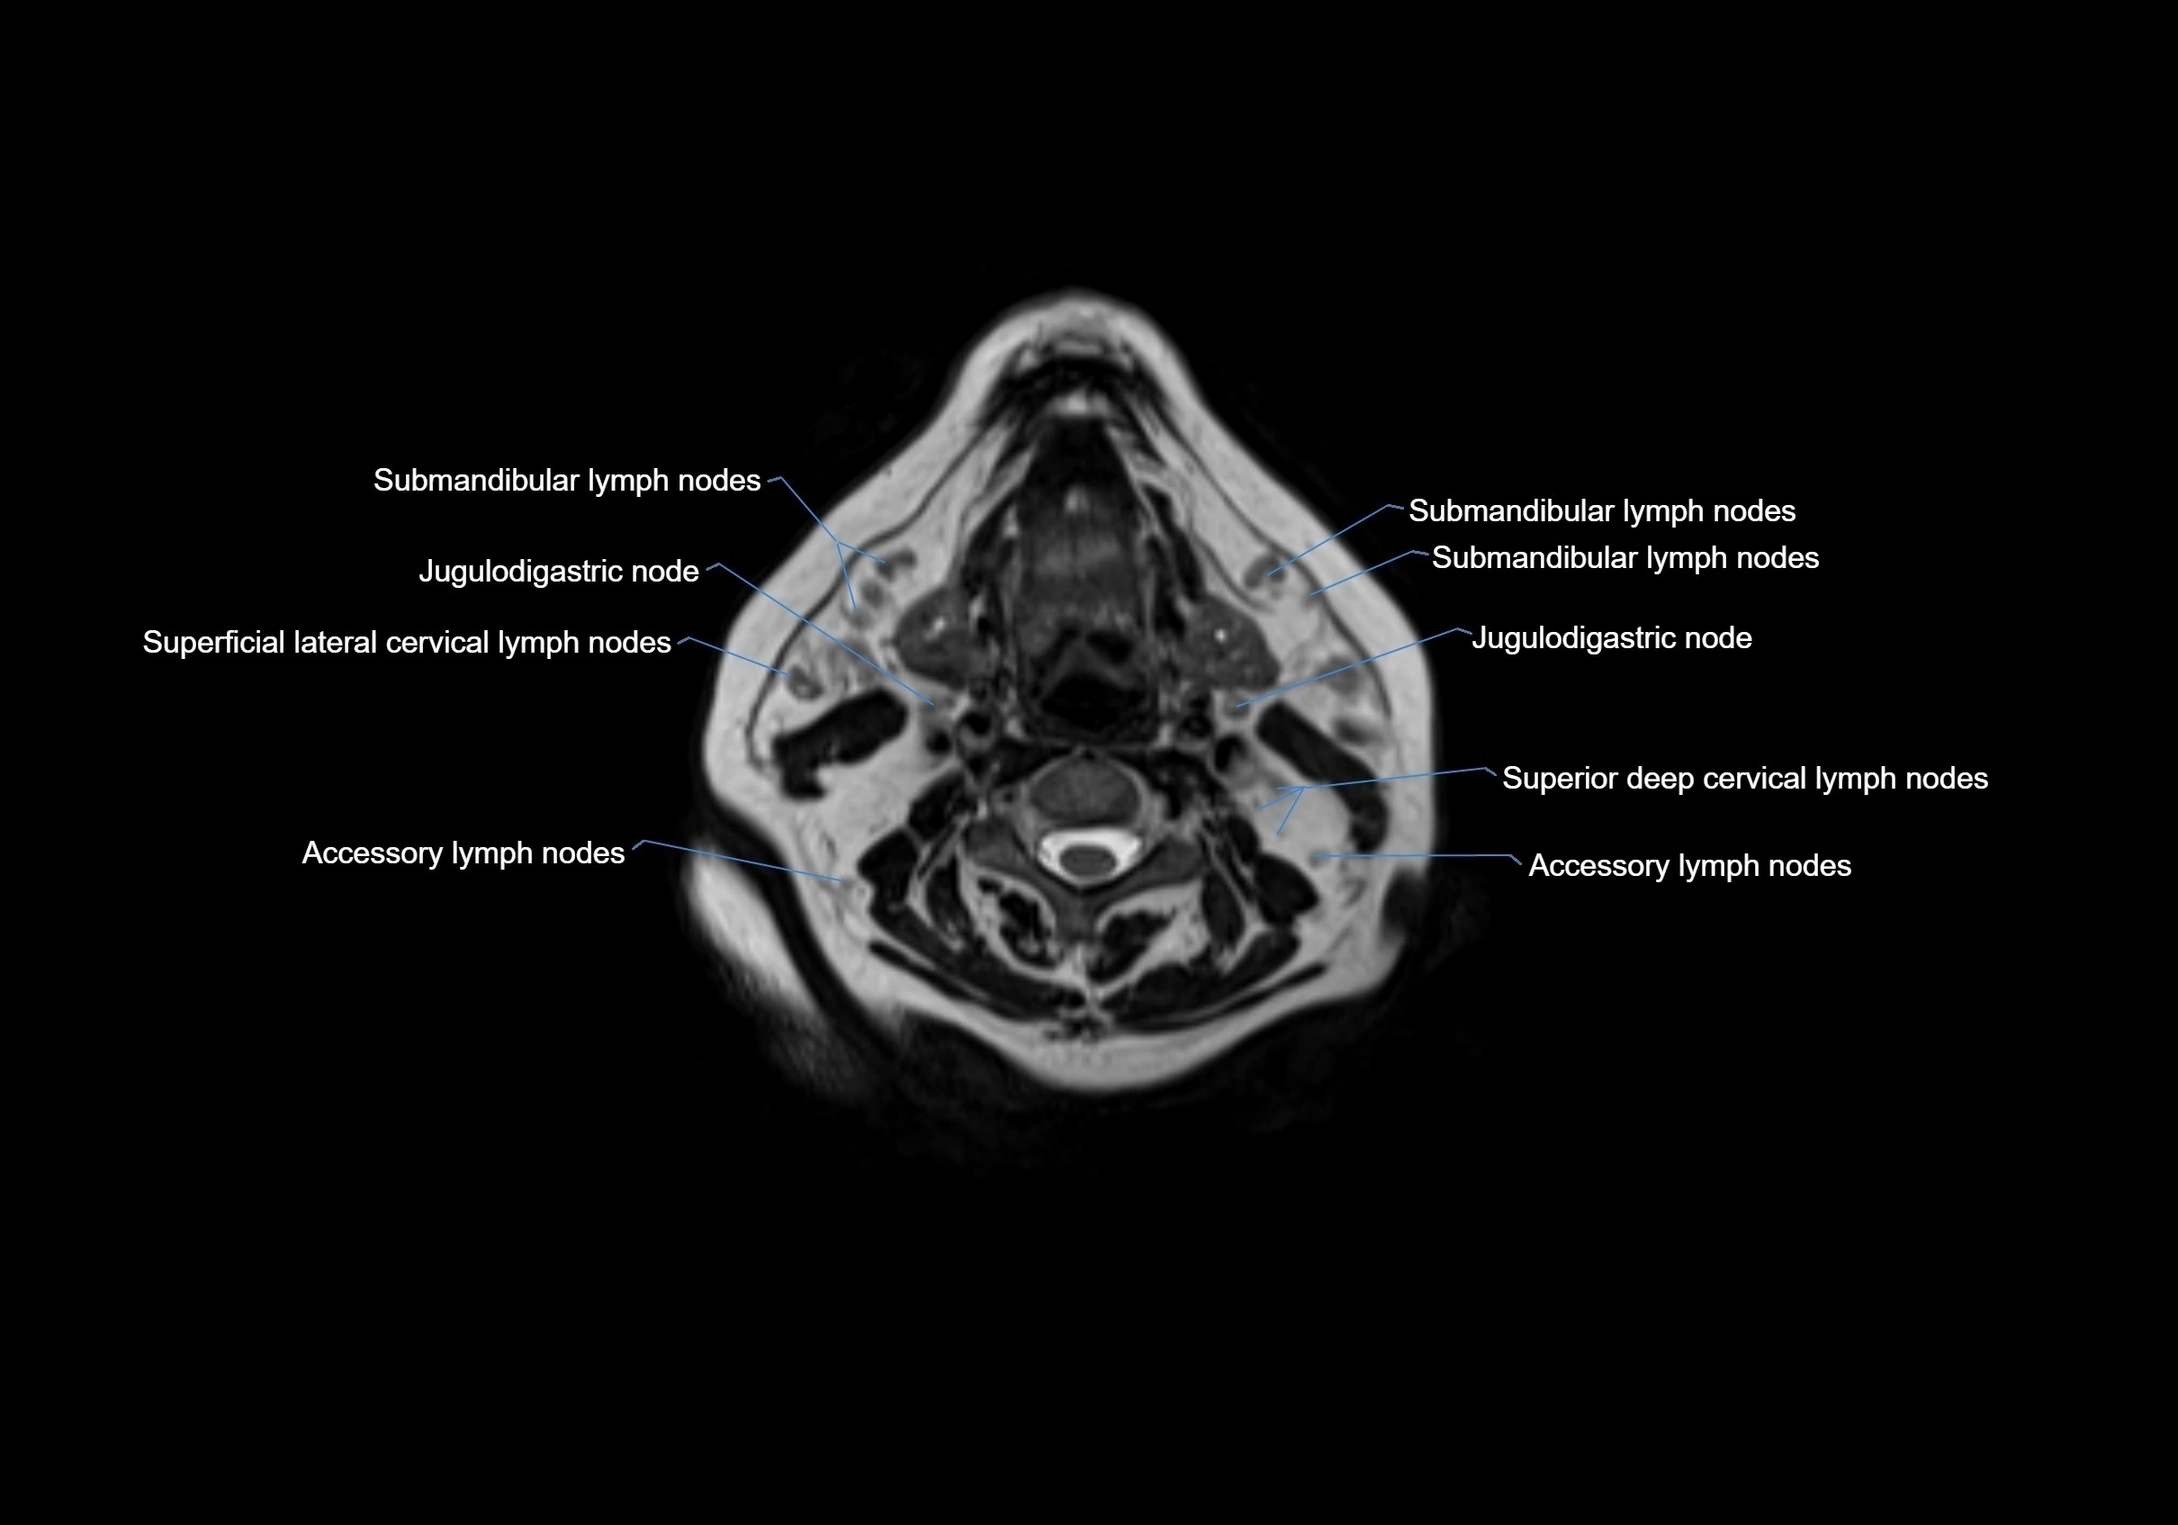

Location

• Found along primary lymph node chains, including preauricular, submandibular, parotid, and occipital regions

• Embedded in subcutaneous fat or superficial fascia, often lateral or posterior to primary nodes

• Variable in number; may occur unilaterally or bilaterally, depending on individual anatomy

MRI Appearance

T1-weighted images:

• Normal accessory nodes appear as small, oval hypointense to intermediate signal structures within subcutaneous fat

• Surrounded by hyperintense fat, enhancing contrast for visualization

• Pathological nodes may appear enlarged or rounded, sometimes with cortical thickening

T2-weighted images:

• Nodes show intermediate signal, with surrounding fat bright

• Useful for detecting edema, inflammation, or infiltration

• Fatty hilum may appear slightly hyperintense relative to cortex

MRI images

image